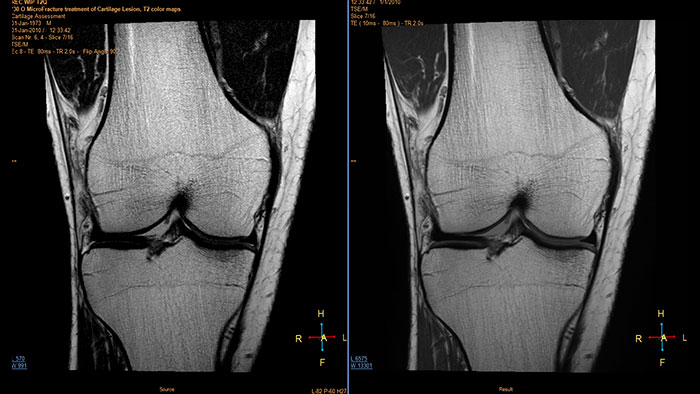

Visualize cartilage structures

Enables the visualization of cartilage structures integrated with color-coded T2 maps. Positioning of cartilage-shaped, layered region of interest is used to assess variation of T2 values across the cartilage depth to determine the degradation of the cartilage.

Benefits